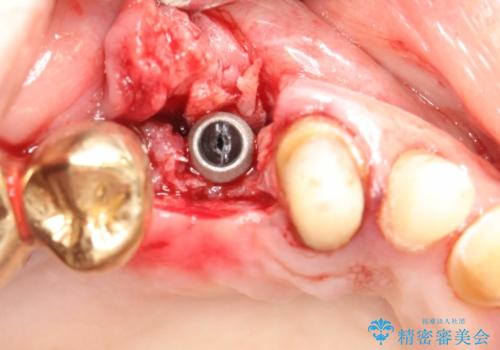

骨が薄く、インプラントの径に耐え得ないと判断したためスプリットクレストにより骨幅を拡大しインプラントを埋入した。

スプリットクレストやリッジエキスパンジョンといった方法は、骨が薄く、細い場合に、割線を設定し、狭い骨幅を拡大すると同時にインプラントを埋入することができます。

インプラントの種類:Bicon